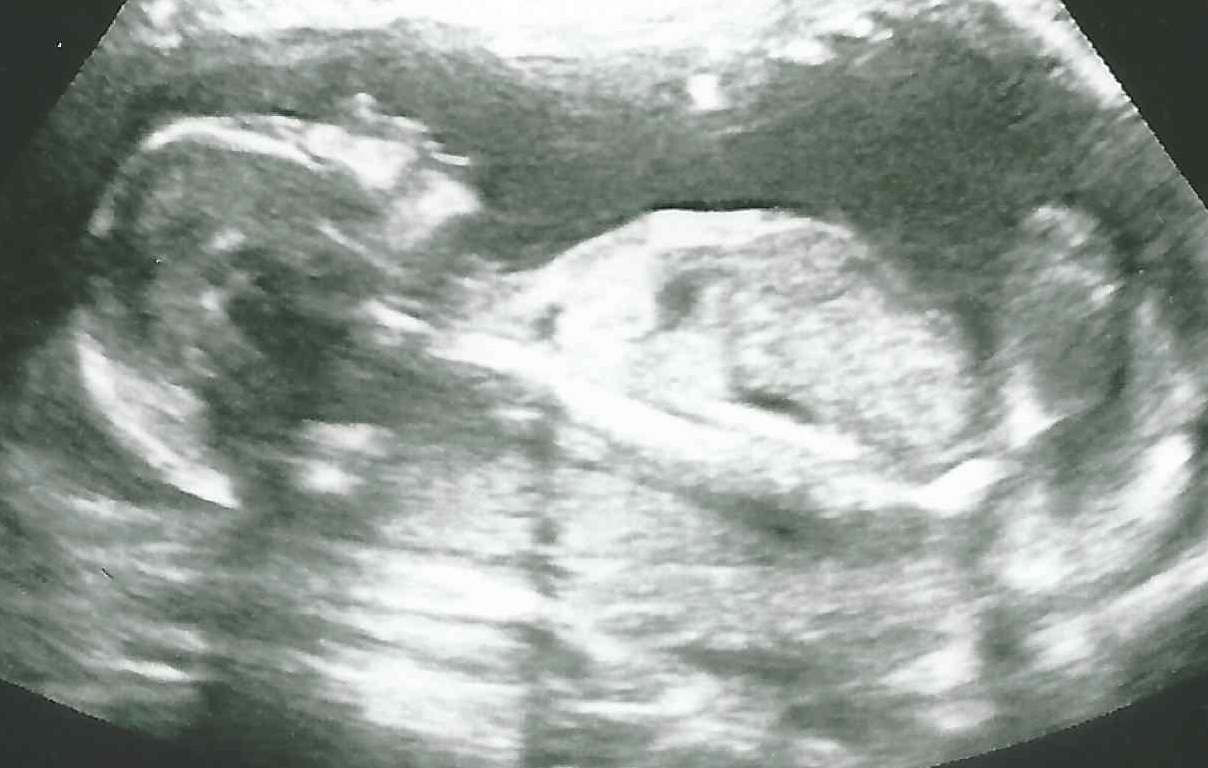

21 weken

Een echo na 21 weken.